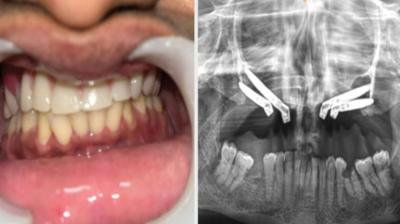

एम्स भोपाल डेंटल टीम ने लिखा इतिहास, इंटरनेशनल जर्नल में केस भेजा

6 Sep, 2025 10:00 PM IST | DUNIAABHIABHI.COM

एम्म में जटिल सर्जरी को सफलतापूर्वक अंजाम दिया है। इस सर्जरी में ट्यूमर के कारण काटे गए निचले जबड़े को पैर की हड्डी से दोबारा बनाया गया और उसमें 13...